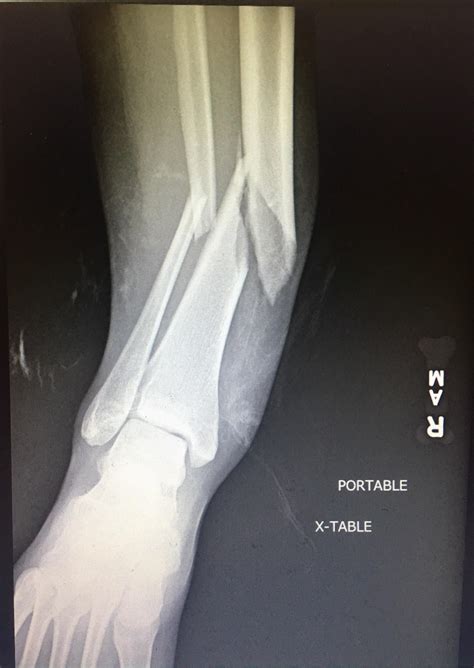

Diagnosing a Broken Fibula and Tibia

Diagnosing a fracture involves a combination of physical examination and imaging tests. The process typically includes:

• Physical Examination: A healthcare provider will assess the injured area for swelling, deformity, and tenderness.

• X-rays: These are the primary imaging tool used to confirm the presence and type of fracture.

• CT Scans: For more detailed images, especially in complex fractures.

• MRI Scans: To evaluate soft tissue damage and assess the extent of the injury.